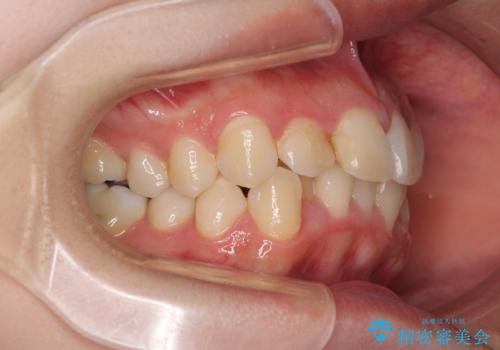

- 上下のデコボコと前歯のクロスバイトを改善したいとのことで来院された患者様です。

極力短期間で治療したいとのことで、ワイヤー装置による矯正治療を行うこととしました。

マウスピースによる矯正治療も提案しましたが、ご自身でのマウスピースの管理の面倒くささと、なるべく早く治療を終えたいとのことで、ワイヤー矯正を選択されました。